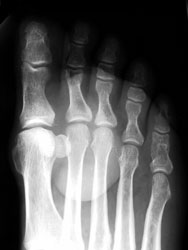

47 year old male with a 6 x 3.5 cm lobulated mass along plantar medial aspect of the 1st toe, which is hypointense on T1W and hyperintense On T2W images. Scattered small foci of hypointensity, representing calcifications is present on all the sequences. The soft tissue mass with small calcifications is also seen on the plain radiograph.